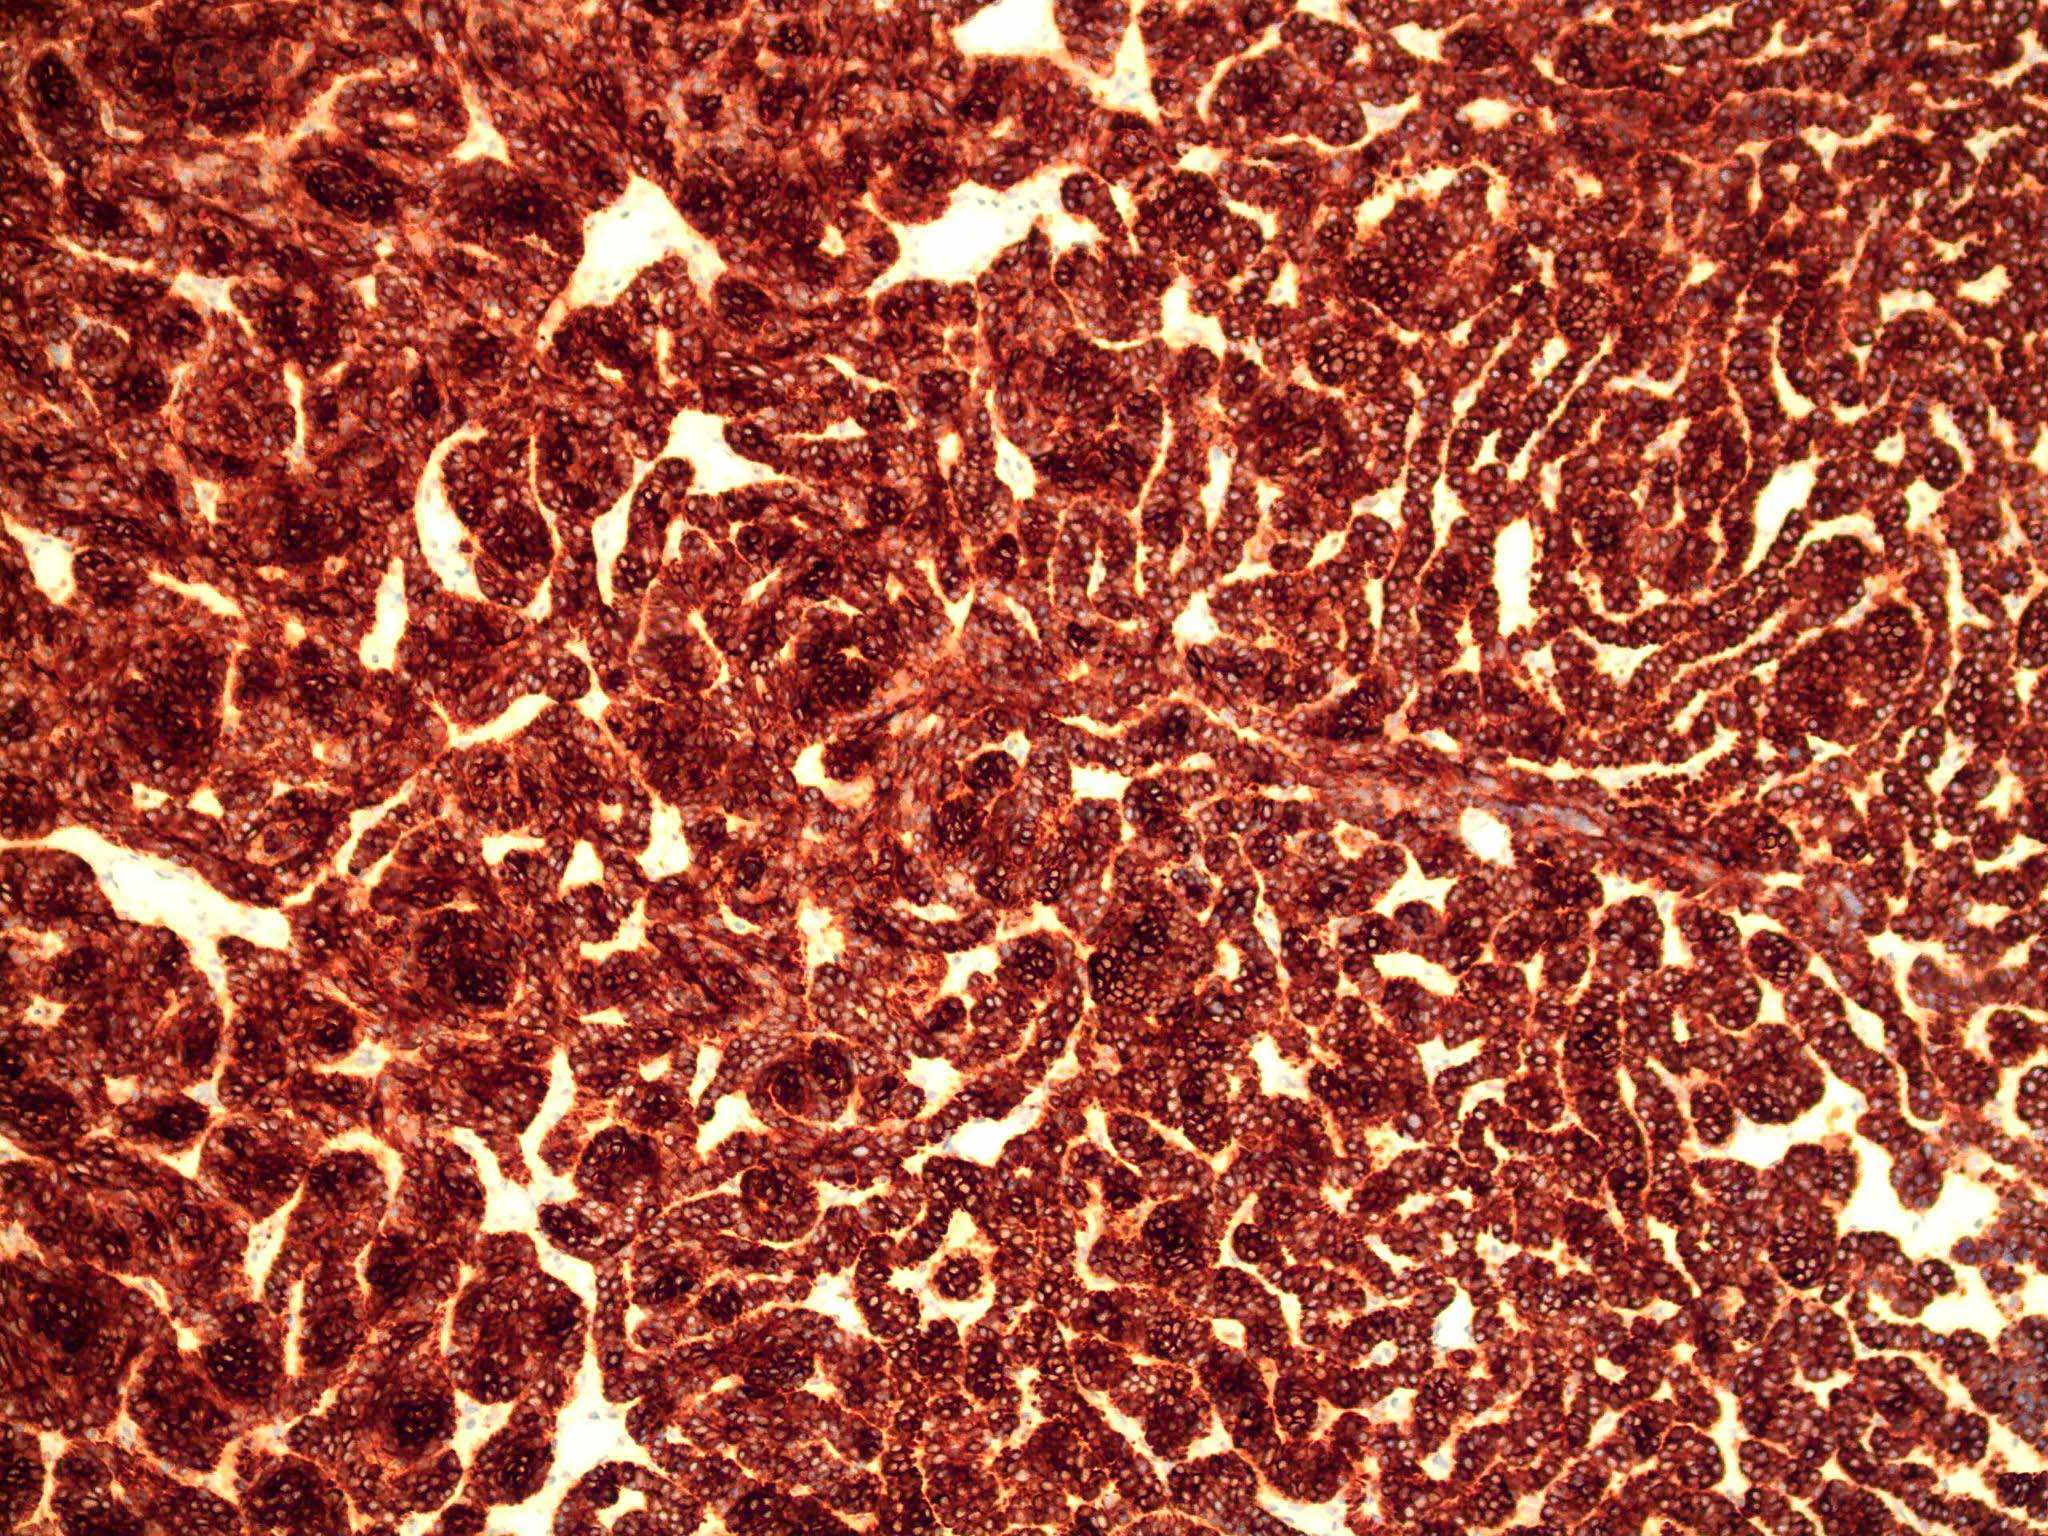

- Nodular and nodulocystic BCC

- Large basaloid lobules with peripheral nuclear palisade

- Lobules may be solid or show central cyst formation due to excessive mucin production

- Fibromyxoid stroma

- Cleft formation between tumor lobules and stroma

- Superficial BCC

- Isolated basaloid lobules projecting from the lower margin of the epidermis

Microscopic (histologic) images

Contributed by Antonina Kalmykova, M.D., Phillip H. McKee, M.D., Sate Hamza, M.D., Eduardo Calonje, M.D.,

Wayne Grayson, M.B.Ch.B., Ph.D., James Sampson, M.B.B.S., M.Sc. and Assia Bassarova, M.D., Ph.D.

Positive stains

- CK AE1 / AE3 (100%), BerEP4 (80 - 100%), p63 (100%), CAM 5.2 (20 - 95%), androgen receptor (33 - 66%), p53 (74.5 - 83%), 34 beta E12 (high molecular weight CK), BCL2 (diffuse pattern), CD10 (positive in tumor cells, negative in stroma) (Dermatopathology (Basel) 2015;2:15, Arch Pathol Lab Med 2017;141:1490, Rom J Morphol Embryol 2018;59:1115, Am J Pathol 1992;141:25)